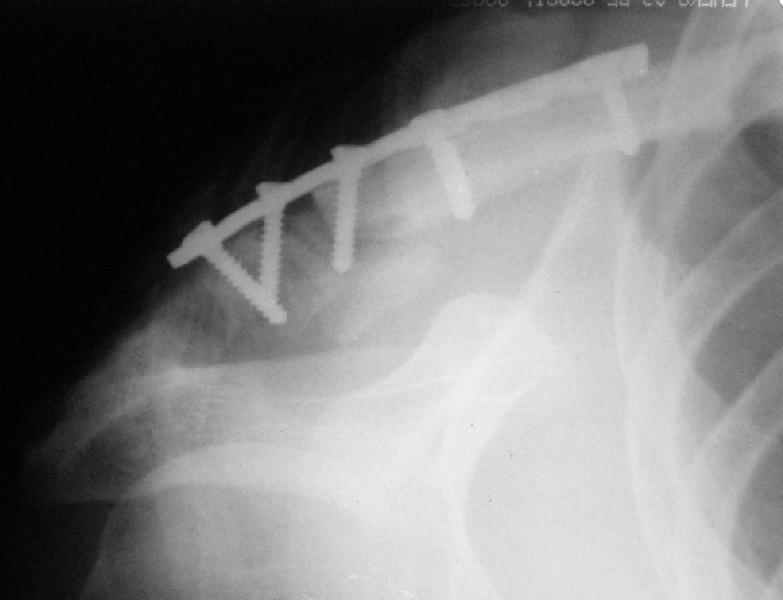

Сегодня прооперировал больного - накостный остеосинтез реконструктивной пластиной с ааллотендопластикой кл-кл связки.

На операции - обширная межотломковая ткань - мобилизовал проксимальный отломок без иссечения м-отломк.ткани, резекция выступающего конца( в последующем использовал как трансплантат).

После мобилизации проксимального отломка достигнут контакт в нижней части . 2 винта в дистальном отломке + петля аллосухожилия, проведенная через канал в проксимальном отломке должна нейтрализовать смещающие силы - надеюсь.

По всему видно, что остеосинтез выполнен неряшливо: неправильное предоперационное планирование и недостаточная и нестабильная, в перспективе, фиксация. Надо начать все сначала.